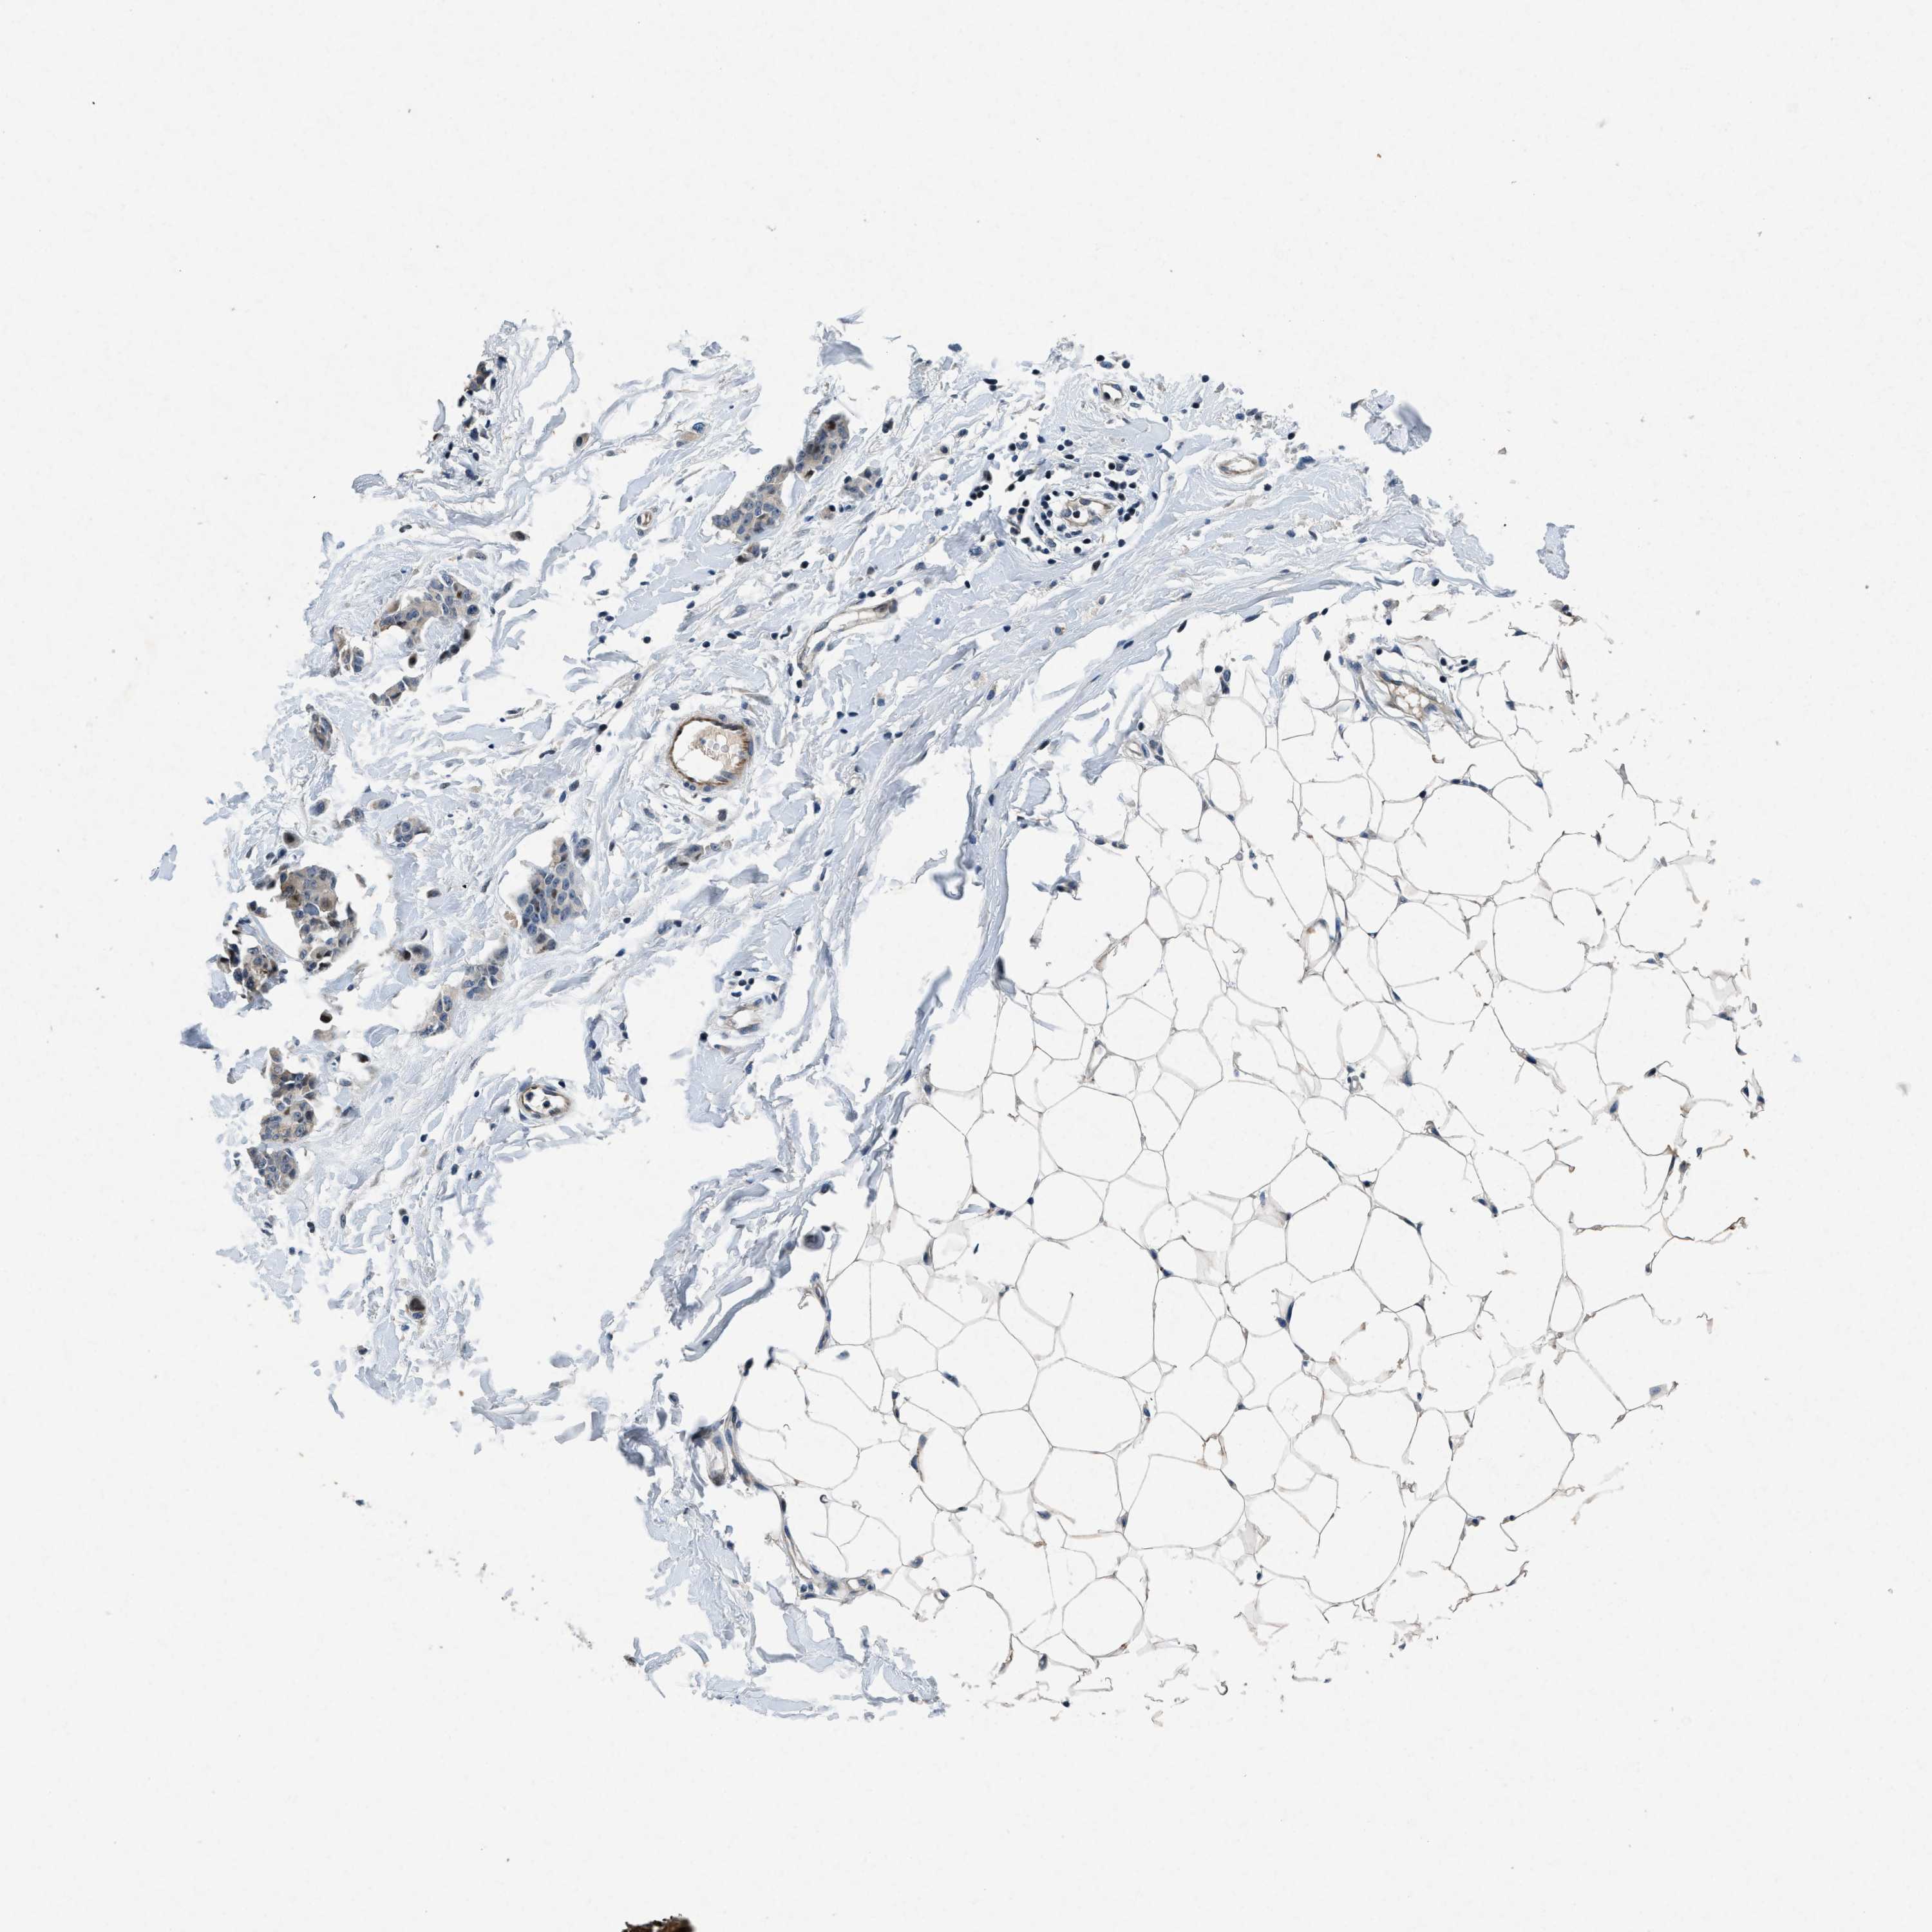

CANCER BREAST CANCER Show tissue menu

BRCA TCGA BRCA VALIDATION PROTEIN EXPRESSION